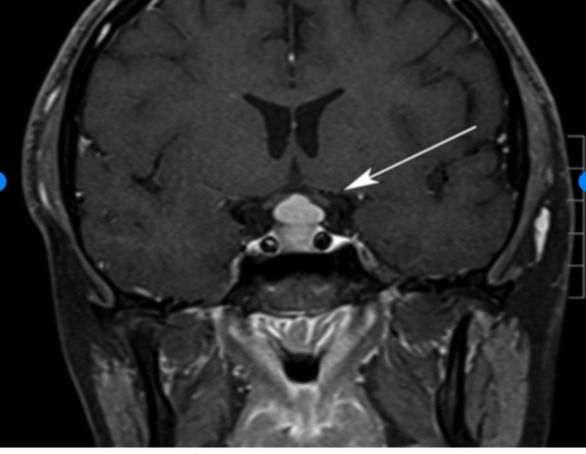

- гиперплазия (увеличение) гипофиза — таким образом организм адаптируется к высокой потребности в ТТГ на фоне снижения тироксина;

![Гиперплазия гипофиза [19] Гиперплазия гипофиза [19]](/media/bolezny/miksedema/giperplaziya-gipofiza-19_s.jpeg?dummy=1764078551443)

Гиперплазия гипофиза [19]